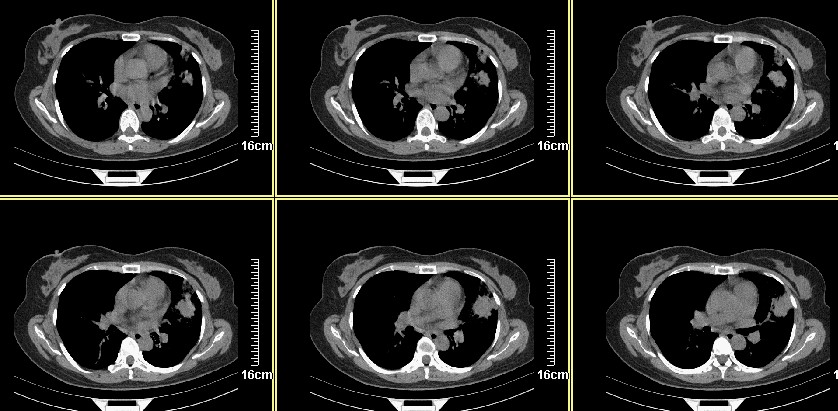

一周之后 复查结果 5mm扫描 40多岁 我们医院的护士

左肺上叶肿块,肺窗周围有“晕征”,纵隔窗有毛刺,临床资料???只能考虑占位???

好像和8248是同一个人的病例吧??呵呵,8248大家都认为是感染,现在又都认为是肺癌,图像小了一点,诊断结果就差别这么大。

病灶分明小多多了